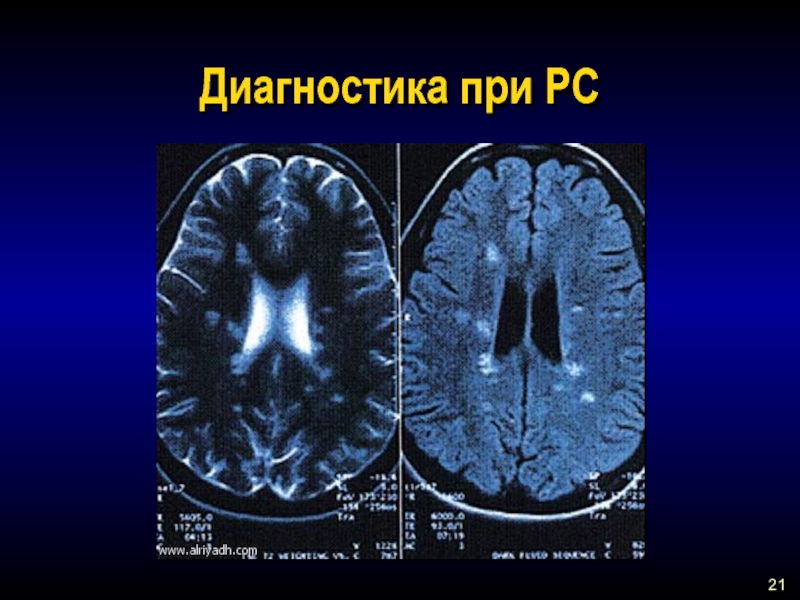

Демиелинизирующие заболевания мозга: МРТ изображения